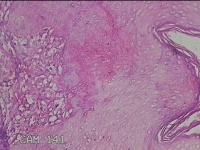

右侧腰臀部包块

性别

女

年龄

44岁

临床诊断

臀部良性肿瘤

一般病史

发现右侧腰臀部包块1个月余。

标本名称

大体所见

灰白粉红色包块0.8x0.3x0.2cm一个,表面光滑。

良性病变。